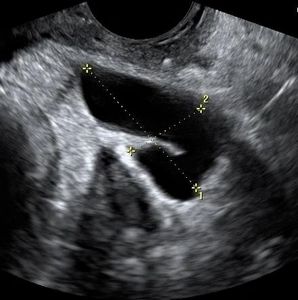

This malformation occurs when the uterine cavity is divided by a septum protruding from the fundus, but keeps the normal outer shape intact. A septate uterus is a common anomaly in women with a history of miscarriages and infertility. The septum is quite variable in length, but should be at least 1.5 cm. It forms a V shape, unlike the rounded U shape of an arcuate uterus. In some cases, the septum completely divides the uterine cavity and cervix into two halves. Resection of the septum can improve fertility and reduce the risk of preterm delivery for some patients.

Bicornuate uterus appears similar to septated uterus, but the outer fundus no longer has the normal rounded shape. Instead, the outer shape shows a mid indentation at least 1cm and a wide intercornual (tube) distance that can be appreciated via hysteroscopy, as well as laparoscopy. A bicornuate uterus cannot be treated with simple resection and therefore surgery is not indicated. However, there is an increased risk of recurrent pregnancy loss, cervical incompetence, and preterm delivery. Many patients are told they have a bicornuate uterus when, in fact, they may have an arcuate uterus or septated uterus.

This form of uterine anomaly occurs when the uterus is predominantly formed by just one of the two paired Müllerian ducts. This abnormality has been shown to have significantly greater chance of infertility, miscarriage, and preterm delivery. On coronal 3D images, the uterine cavity no longer shows a normal triangular shape, but rather assume a banana shape. However, unicornuate uterus is typically missed with standard 2D ultrasound. In part for this reason, all fertility patients should have 3D coronal images of the uterus.

All of the uterine abnormalities described here can be seen with coronal 3D ultrasound, while they are often misdiagnosed, or even missed entirely with standard 2D ultrasound. Therefore, all fertility patients should have 3D scans of the uterus.